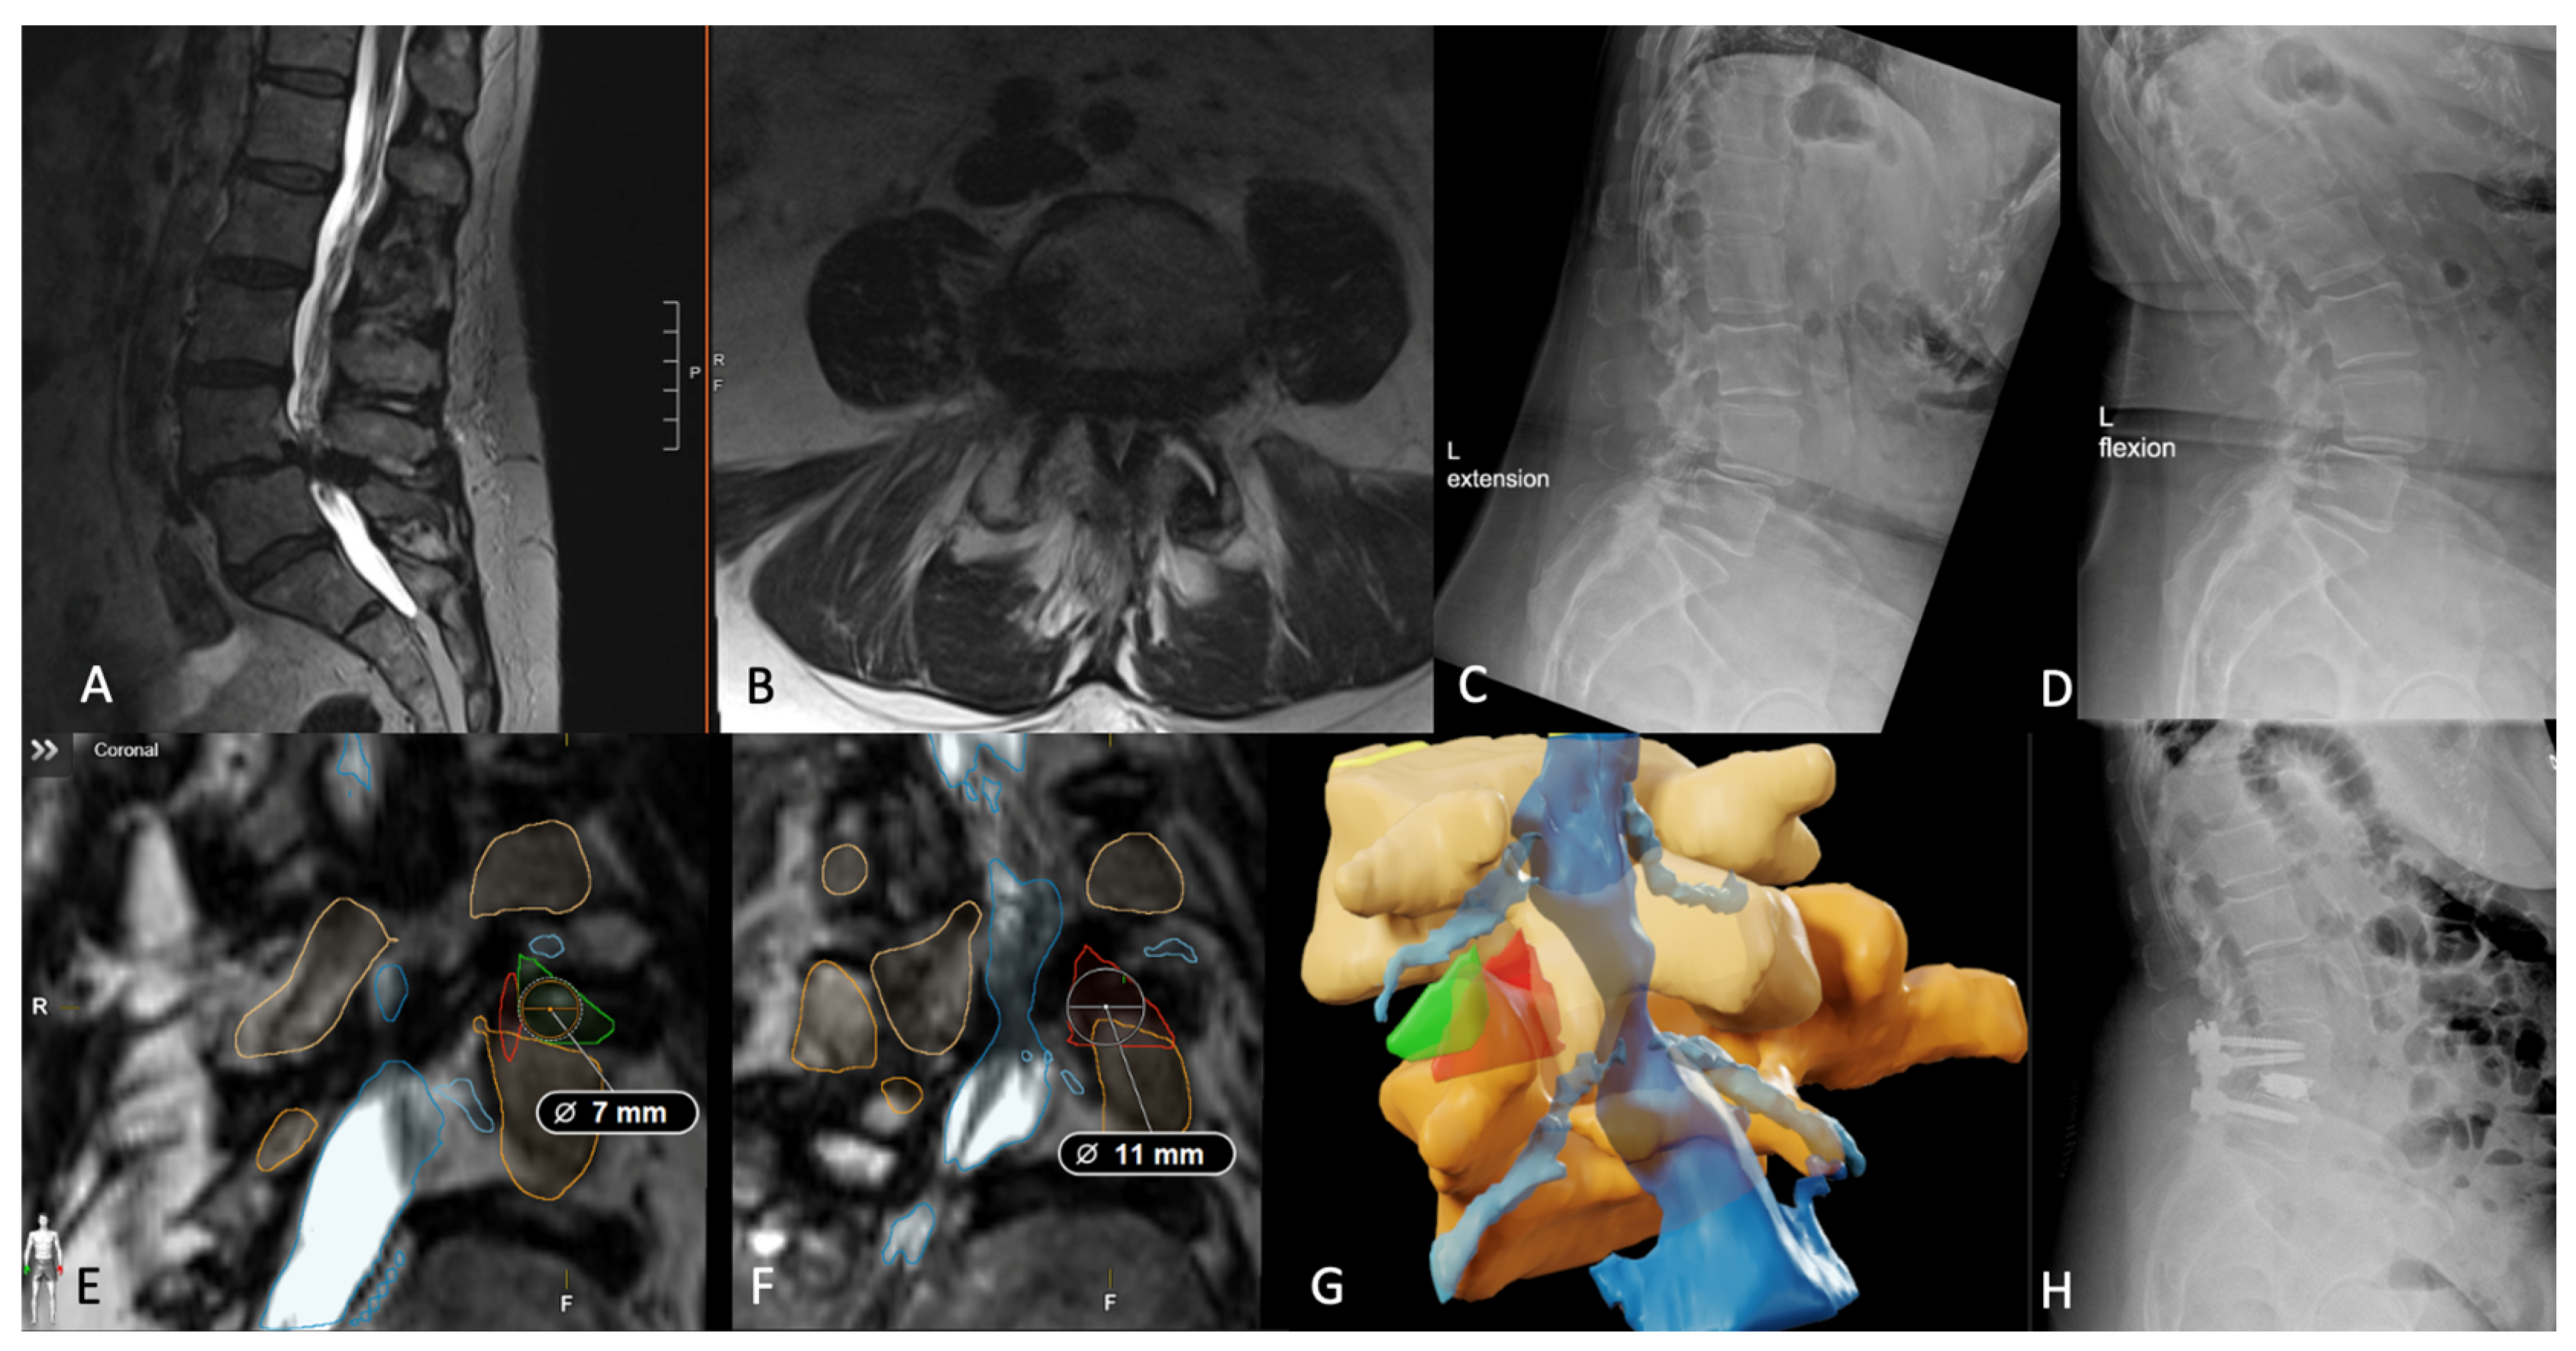

- Tabarestani, T.Q.; Salven, D.S.; Sykes, D.A.W.; Bardeesi, A.M.; Bartlett, A.M.; Wang, T.Y.; Paturu, M.R.; Dibble, C.F.; Shaffrey, C.I.; Ray, W.Z.; et al. Using Novel Segmentation Technology to Define Safe Corridors for Minimally Invasive Posterior Lumbar Interbody Fusion. Oper. Neurosurg. 2023. [Google Scholar] [CrossRef] [PubMed]

- Tabarestani, T.Q.; Sykes, D.A.W.; Kouam, R.W.; Salven, D.S.; Wang, T.Y.; Mehta, V.A.; Shaffrey, C.I.; Wiggins, W.F.; Chi, J.H.; Abd-El-Barr, M.M. Novel Approach to Percutaneous Lumbar Surgeries via Kambin’s Triangle-Radiographic and Surgical Planning Analysis with Nerve Segmentation Technology. World Neurosurg. 2023, 177, e385–e396. [Google Scholar] [CrossRef] [PubMed]

- Tabarestani, T.Q.; Sykes, D.A.W.; Maquoit, G.; Wang, T.Y.; Ayoub, C.M.; Shaffrey, C.I.; Wiggins, W.F.; Abd-El-Barr, M.M. Novel Merging of CT and MRI to Allow for Safe Navigation into Kambin’s Triangle for Percutaneous Lumbar Interbody Fusion-Initial Case Series Investigating Safety and Efficacy. Oper. Neurosurg. 2023, 24, 331–340. [Google Scholar] [CrossRef] [PubMed]